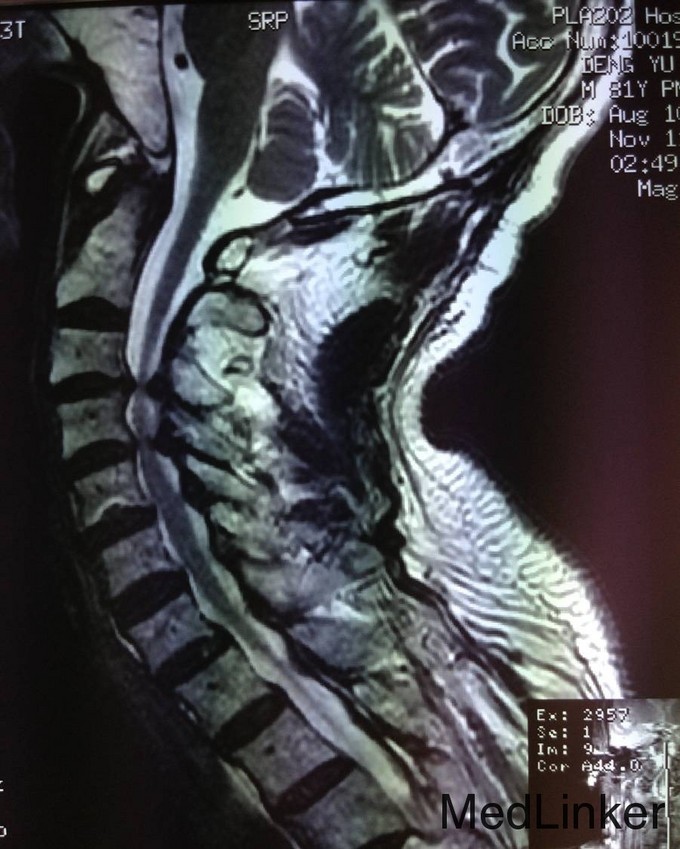

患者男,81岁,自述于1个月前出现双上肢感觉减退,发胀,以左侧为重,后来加重,左侧握力减退,于201医院就诊,行颈椎MR检查,提示为颈3-4、4-5间盘突出,为求进一步治疗就诊于我院,患者病来饮食、睡眠佳。大小便正常,体重无明显变化。

颈椎生理弯曲消失,活动度正常。双上肢感觉减退。双手握力(R5级,L4级),伸肘肌力(R5级,L5级),屈肘肌力(R5级,L5级),Hoffman(R-,L+)桡动脉搏动有力,末梢血运良。

诊断:颈椎病,颈椎间突出,高血压病 患者入院后完善相关检查,请相关科室及麻醉科会诊,医院医务部审批后,查无其他手术禁忌症,于全麻下行颈椎后路单开门椎管扩大减压侧块螺钉内固定术。术后给予患肢雾化祛痰,抗炎,消肿,营养神经,接骨等对症治疗。术后患者在颈领的保护下可下地行走,术后14天拆线后予以出院,